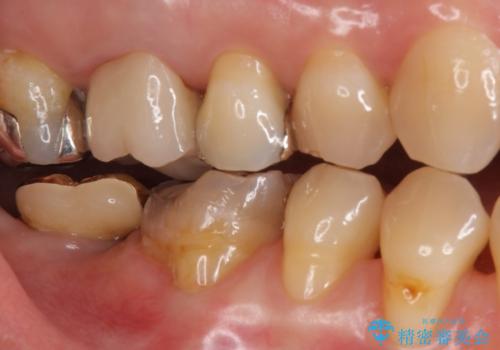

- 昔つめた材料が欠けたこと、歯の捻転を主訴に来院されました。

矯正治療の希望はなかったため、被せ物で歯の形を修正することになりました。

不適合だった詰め物の裏側に大きな虫歯がありました。

セラミックインレーやアンレーでは強度に不安が残るため、クラウンでの修復処置としました。

クラウンでは歯のがたつきを修正することもできます。

虫歯の除去と歯の捻転の両方を解決することができました。